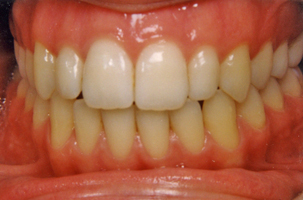

3. Μεταχειρουργική ορθοδοντική θεραπεία:

Αφού τελειώσει η περίοδος της ακινητοποίησης, ο ασθενής επιστρέφει στον ορθοδοντικό ο οποίος πλέον ασχολείται με την μεταχειρουργική ορθοδοντική διευθέτηση των δοντιών. Καθώς έχει ήδη αποκατασταθεί η τελική καλή σχέση των γνάθων μεταξύ τους, είναι πλέον δυνατές και κάποιες μικρομετακίνησεις ακριβείας των δοντιών προκειμένου να επιτευχθεί μια σταθερή και λειτουργική σύγκλειση. Η διάρκεια της μεταχειρουργικής ορθοδοντικής θεραπείας ποικίλλει από 4-12 μήνες.

Οι μεικτές αυτές θεραπείες είναι εξαιρετικά εντυπωσιακές δεδομένου ότι ευνοούν όχι μόνο το στόμα και το χαμόγελο αλλά και το πρόσωπο συνολικά. Οι ασθενείς διανύουν ένα μακρύ δρόμο αλλά το τελικό αποτέλεσμα επηρεάζει τόσο θετικά την ζωή τους που αποζημιώνονται.